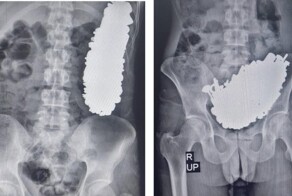

19-летняя пациентка поступила в ГКБ №15 в Москве с новообразованием гигантских размеров - 167 х 66 х 238 мм.

Девушку периодически беспокоили тянущие боли в нижних отделах живота. Компьютерная томография подтвердила наличие кистозного образования над мочевым пузырем размерами 167 х 66 х 238 мм. Уровень онкомаркеров был в норме.